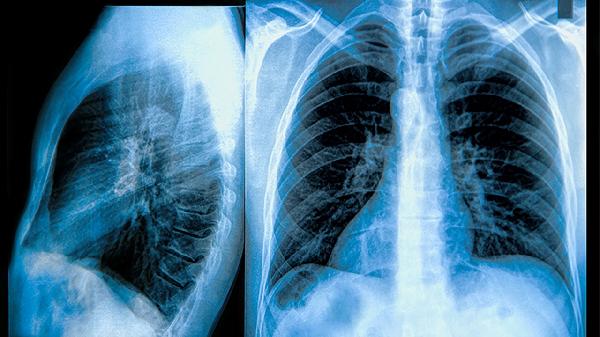

消癌平分散片的主要成分是从萝藦科植物通关藤提取的抗肿瘤活性物质,具有抑制肿瘤细胞增殖、诱导凋亡的作用。临床观察显示,对于肺癌、肝癌、胃癌等实体肿瘤,部分患者用药后可出现病灶稳定或缩小的现象,同时能改善化疗引起的白细胞减少、乏力等症状。该药联合常规放化疗使用时,可能帮助减轻恶心呕吐、骨髓抑制等不良反应。